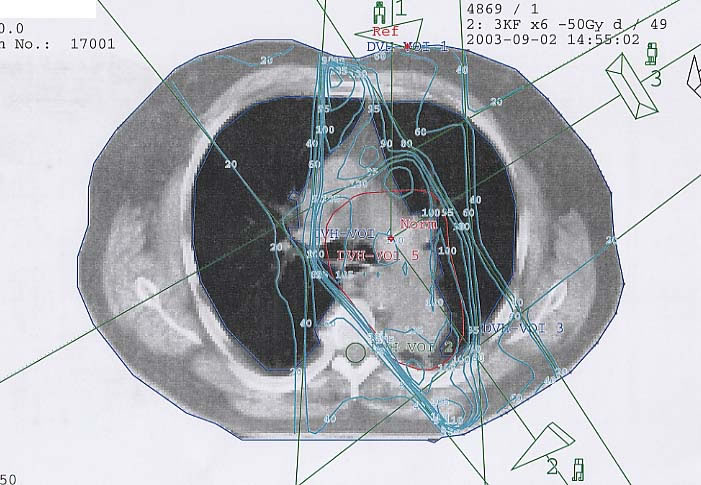

Bronchialkarzinom: Bestrahlungsplan